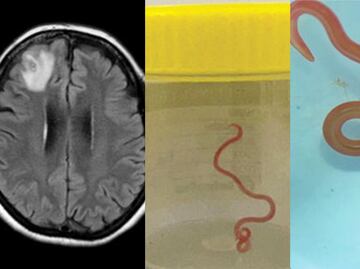

Según explicó la agencia, las gotas y sus productos derivados no fueron hechos a propósito con sustancias extrañas en su fórmula, sino que se contaminan durante el proceso de fabricación cuando no se siguen procedimientos estériles, cuando hay contaminantes en el entorno como gérmenes, objetos o insectos.

Esta no es la primera vez que se alerta por productos contaminados para los ojos. A inicios de año la FDA informó que una persona murió y 68 quedaron ciegas por el uso de productos similares contaminados.

Un informe reveló que la marca EzriCare vendió gotas de lágrimas artificiales contaminadas con P. aeruginosa, una bacteria mortal que causa infecciones peligrosas en los hospitales.